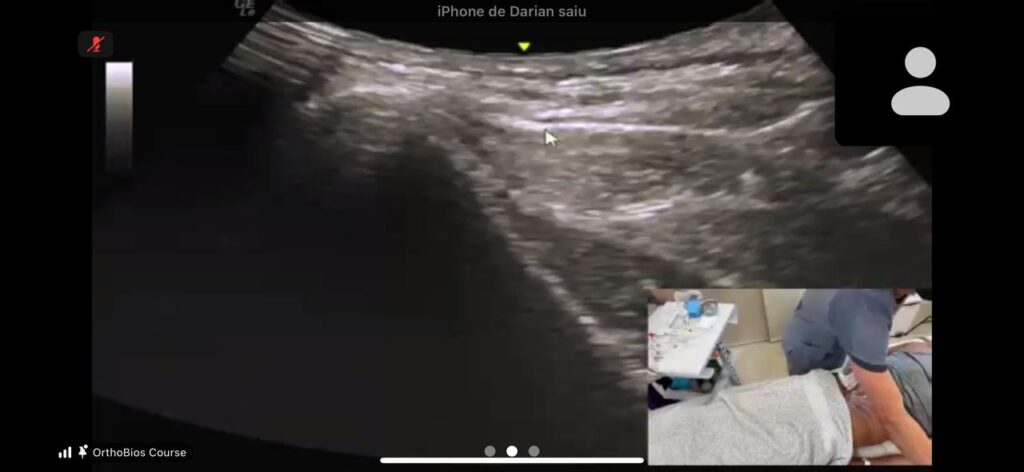

Esse concentrado é então utilizado no tratamento da lesão, com aplicação guiada por imagem para maior precisão.